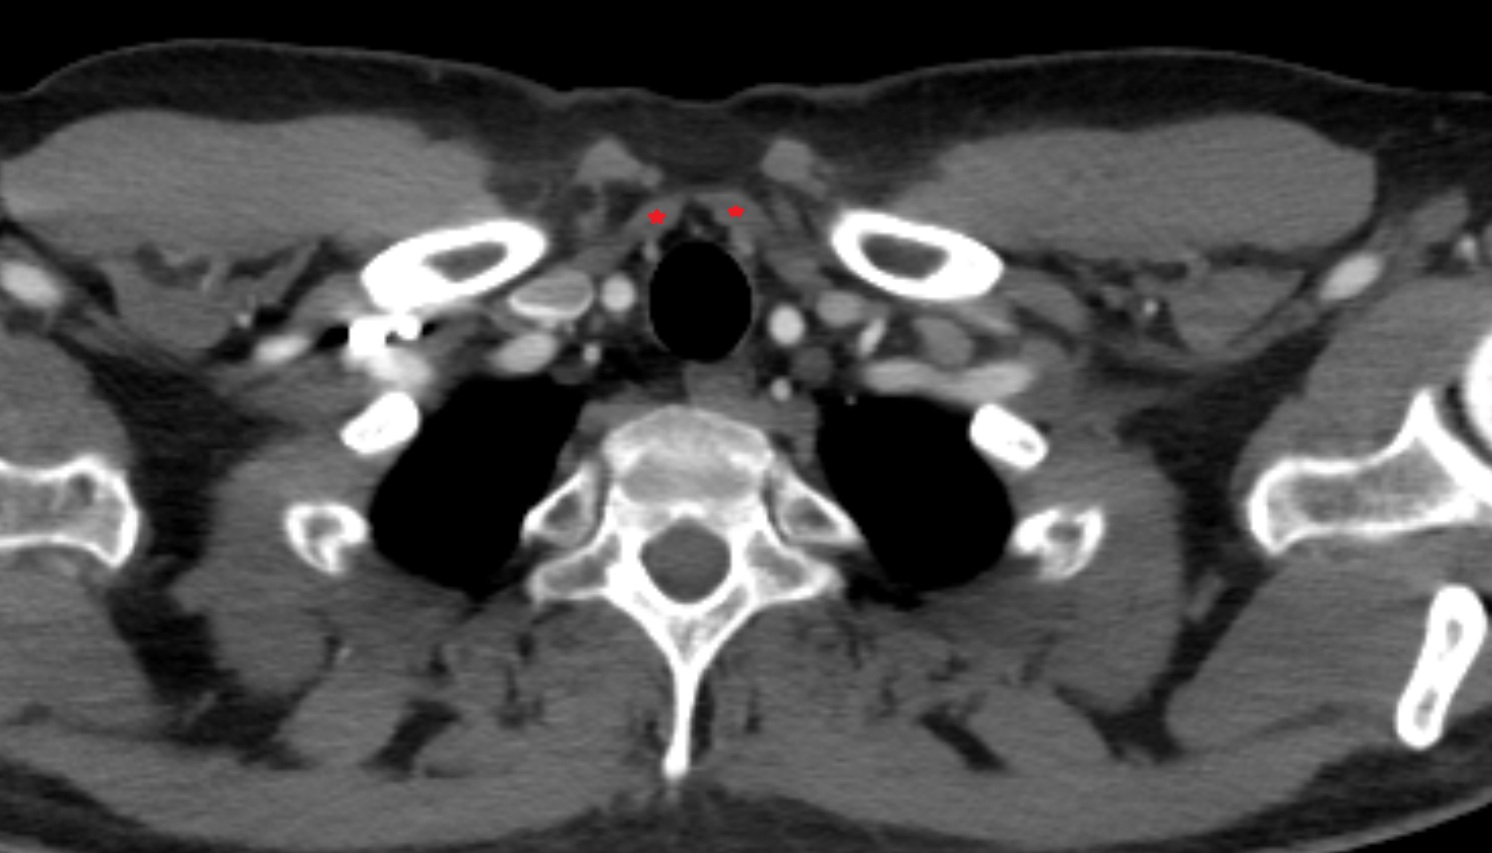

- Common carotid artery

- Internal carotid artery (cervical part)